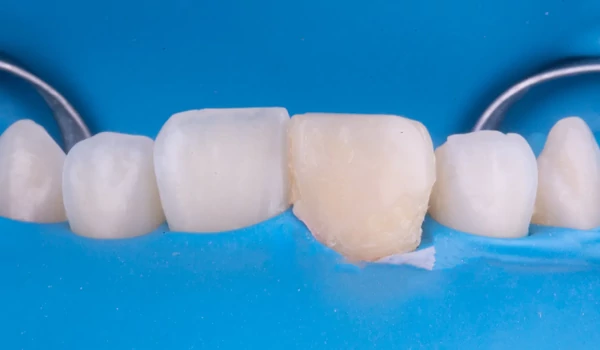

A klinikai beavatkozás lépései1. Izoláció és a régi restauráció eltávolításaA fogat kofferdámmal izolálták, majd eltávolították a rosszul illeszkedő régi kompozit restaurációt. Megállapították, hogy a gyökértömés túl koronálisan volt levágva, ami elszíneződés kockázatát rejti magában. Ezért a gutta-perchát a megfelelő biológiai szintre visszaszivattyúzták egy downpack eszköz segítségével kuraraynoritake.eu. |

2. ábra. A munkaterület izolálása kofferdámmal: frontális nézet. |

3. ábra. A munkaterület izolálása kofferdámmal: okkluzális (rágófelszíni) nézet. |